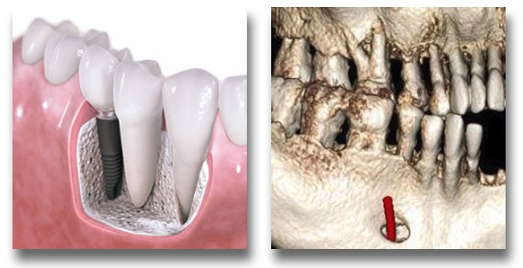

Oral & maxillofacial surgery

• Precisely determine position of impacted teeth

• Get stunning 3D reconstructed images to study pathology / trauma in precise detail

• Use the same 3D data to fabricate 3D models

• Asses the entire maxillofacial skeleton prior to major surgical procedure or evaluation of trauma

Periodontics

• Accurate assessment of buccal/labial and palatal/lingual alveolar bone crestal levels

• Accurate reconstruction of intrabony & fenestration defects, dehiscence, and furcation involvement

• Post-operative assessment of bone grafts with superimposition tools quantifying the difference